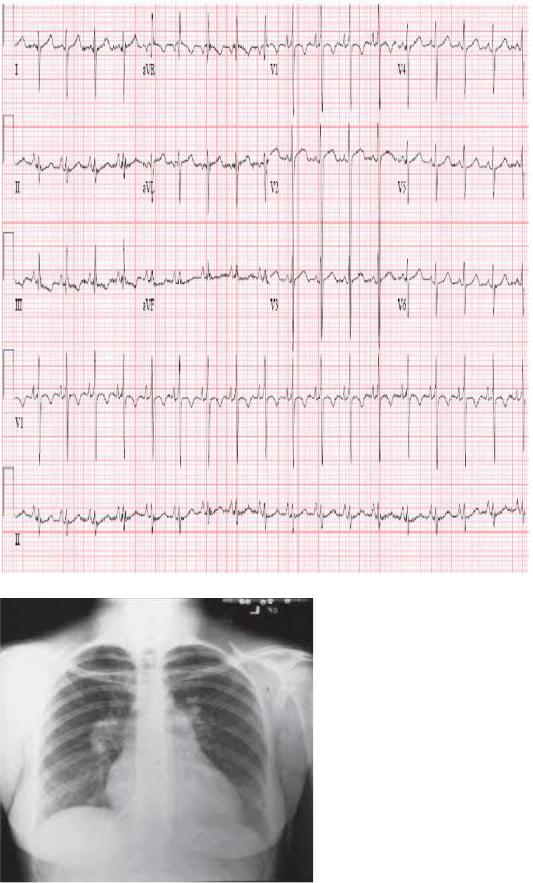

Гемокультура: в одной из 3 проб рост золотистого стафилококка. ЭКГ

Рентгенологическое исследование органов грудной клетки

Вызвала скорую медицинскую помощь (СМП). При осмотре врачом СМП состояние тяжѐлое за счѐт болевого синдрома в грудной клетке, одышки, гипотонии (АД - 100/60, ЧСС – 98 в минуту). Записана электрокардиограмма (ЭКГ) (см. ниже). С некупированным болевым синдромом доставлена в приѐмное отделение.

Объективно: состояние тяжѐлое за счѐт болевого синдрома в грудной клетке, одышки, гипотонии. При осмотре кожные покровы мраморной окраски, холодные, выраженно влажные. Сохраняется одышка в покое, частота дыхания до 28 в минуту, пациентка принимает вынужденную позу полусидя. Аускультативно над всеми лѐгочными полями влажные мелкопузырчатые хрипы. Пульс на лучевых артериях выраженно ослаблен, нитевидный, 120 ударов в минуту. Аускультативно в области сердца ослаблен I тон, тахикардия до 120 в минуту, выслушивается систолический шум на верхушке. Артериальное давление на правой верхней конечности - 80/50 мм рт. ст., на левой верхней конечности - 75/50 мм рт. ст. Отѐков на нижних конечностях нет. По ЭКГ в приѐмном отделении без динамики, по сравнению с пленкой СМП.

Рентгенологически в лѐгких венозный застой III степени, тень сердца расширена

влево.

ЭКГ на этапе СМП.